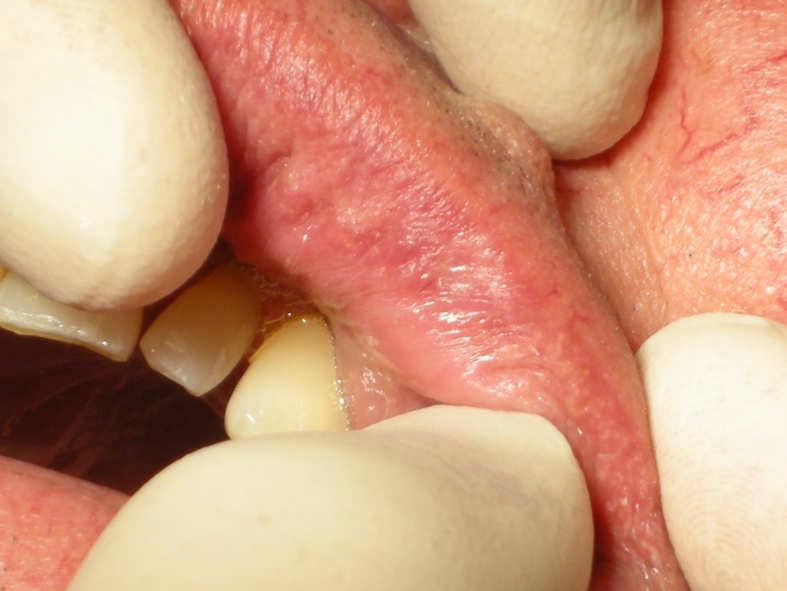

Dr. Valter Pirazzoli

Laser Setting

Diode Laser 810nm

Power: 3.0 - 5,0 Watt, CW

Fibre 400 micron